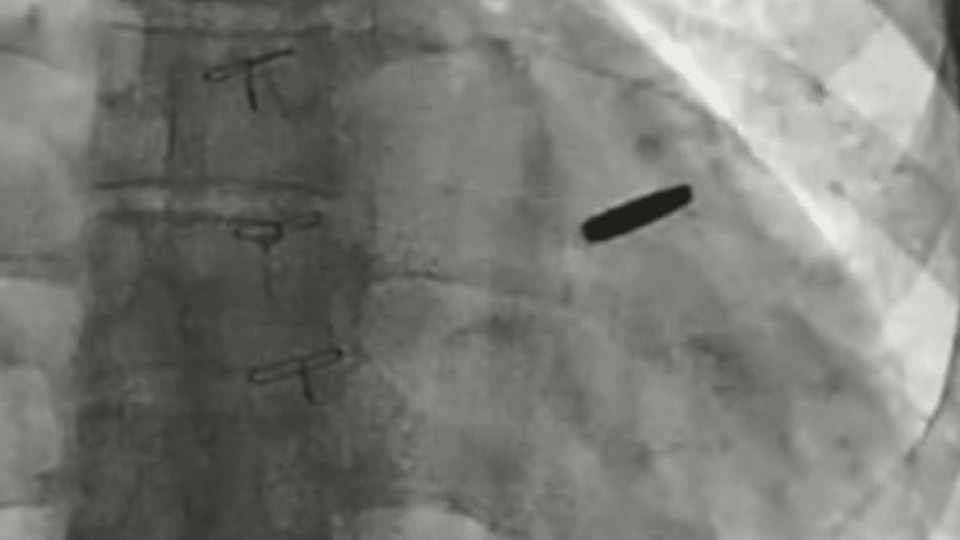

Украински лекари са извадили куршум, заседнал в сърцето на войник, защитавал стоманодобивния завод „Азовстал“ в Мариупол и оцелял три години в руски плен, според Борис Тодуров, директор на Украинския институт по сърдечни заболявания, на 19 септември.

Тодуров каза, че куршумът по чудо е пропуснал жизненоважни структури, което е позволило на боеца да живее с него, забит в сърцето му, в продължение на три години.

„Куршумът вече е изваден. Човекът е имал късмет. Мисля, че ще живее дълъг и щастлив живот“, каза Тодуров, държейки куршума по време на брифинг за пресата.

Лекарите казаха, че куршумът не е причинил сериозни щети през годините, в които е останал заседнал в сърцето.